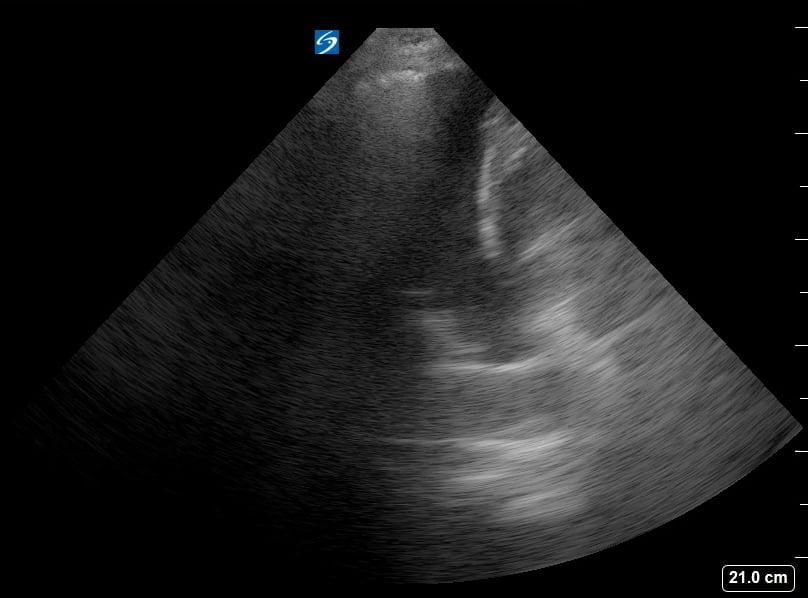

Lung consolidation in medical ultrasound refers to the solidification of lung tissue due to the accumulation of fluid, cells, or other substances, replacing the air within the alveoli. This pathological change commonly indicates conditions like pneumonia or atelectasis. On ultrasound, consolidated lung appears hyperechoic (bright) with a tissue-like echotexture, often resembling the liver (hepatization).

Identifying lung consolidation via ultrasound is crucial for rapid diagnosis and management in acute care settings. This non-invasive imaging technique allows clinicians to visualize air bronchograms (air-filled bronchi within consolidated tissue) and pleural effusions, aiding in differentiation from other lung pathologies. Ultrasound offers a portable and radiation-free alternative for bedside assessment of lung parenchyma, optimizing patient care.